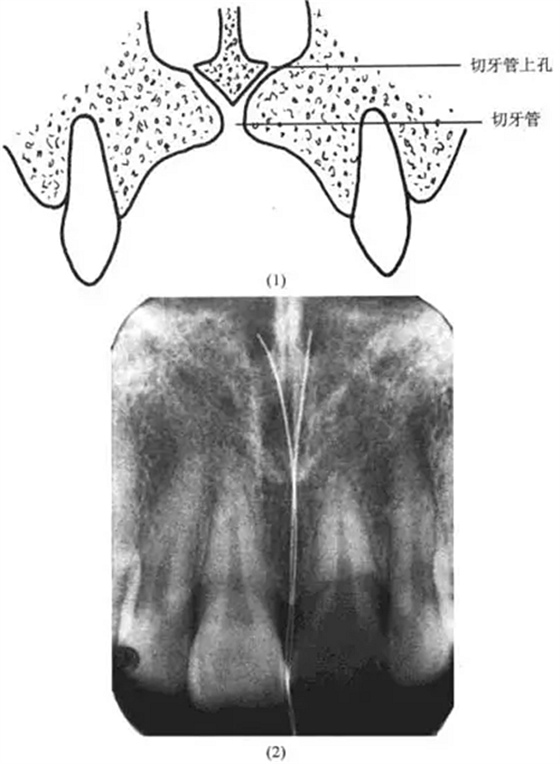

理由:解剖復(fù)習(xí)

切牙孔:在給片上常表現(xiàn)為一界限清楚的圓形、卵圓形密度較低影像,根尖片上切牙孔的位置可位于中切牙牙根之間,靠近牙槽嵴或在根尖平面。

切牙管:終于切牙孔,可見(jiàn)于中切牙的根尖片上。

切牙管上孔:共2個(gè),位于鼻前唇底,與鼻中隔鄰接,根尖片上切牙管上孔的影像可能投射到任何切牙的根端,因而有時(shí)可誤認(rèn)為根尖周病變(圖13-5)

上述病例的診斷可據(jù)此及牙髓活力存在而確診。